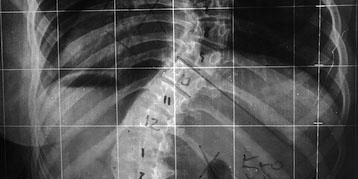

É importante o auxílio de exames de imagem para mensurar a curva e definir o potencial de crescimento.

Através de radiografias simples panorâmicas da coluna vertebral é possível definir a localização e magnitude de cada curva. Também é possível avaliar a situação da cartilagem de crescimento e prognóstico quanto a progressão da curva.